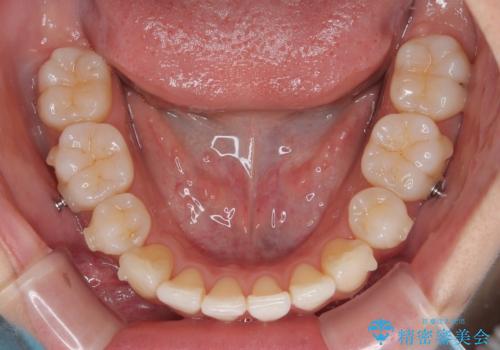

1. 抜歯矯正の軽度後戻りを解消 インビザライン矯正の治療前

2. 抜歯矯正の軽度後戻りを解消 インビザライン矯正の治療中

3. 抜歯矯正の軽度後戻りを解消 インビザライン矯正の治療後